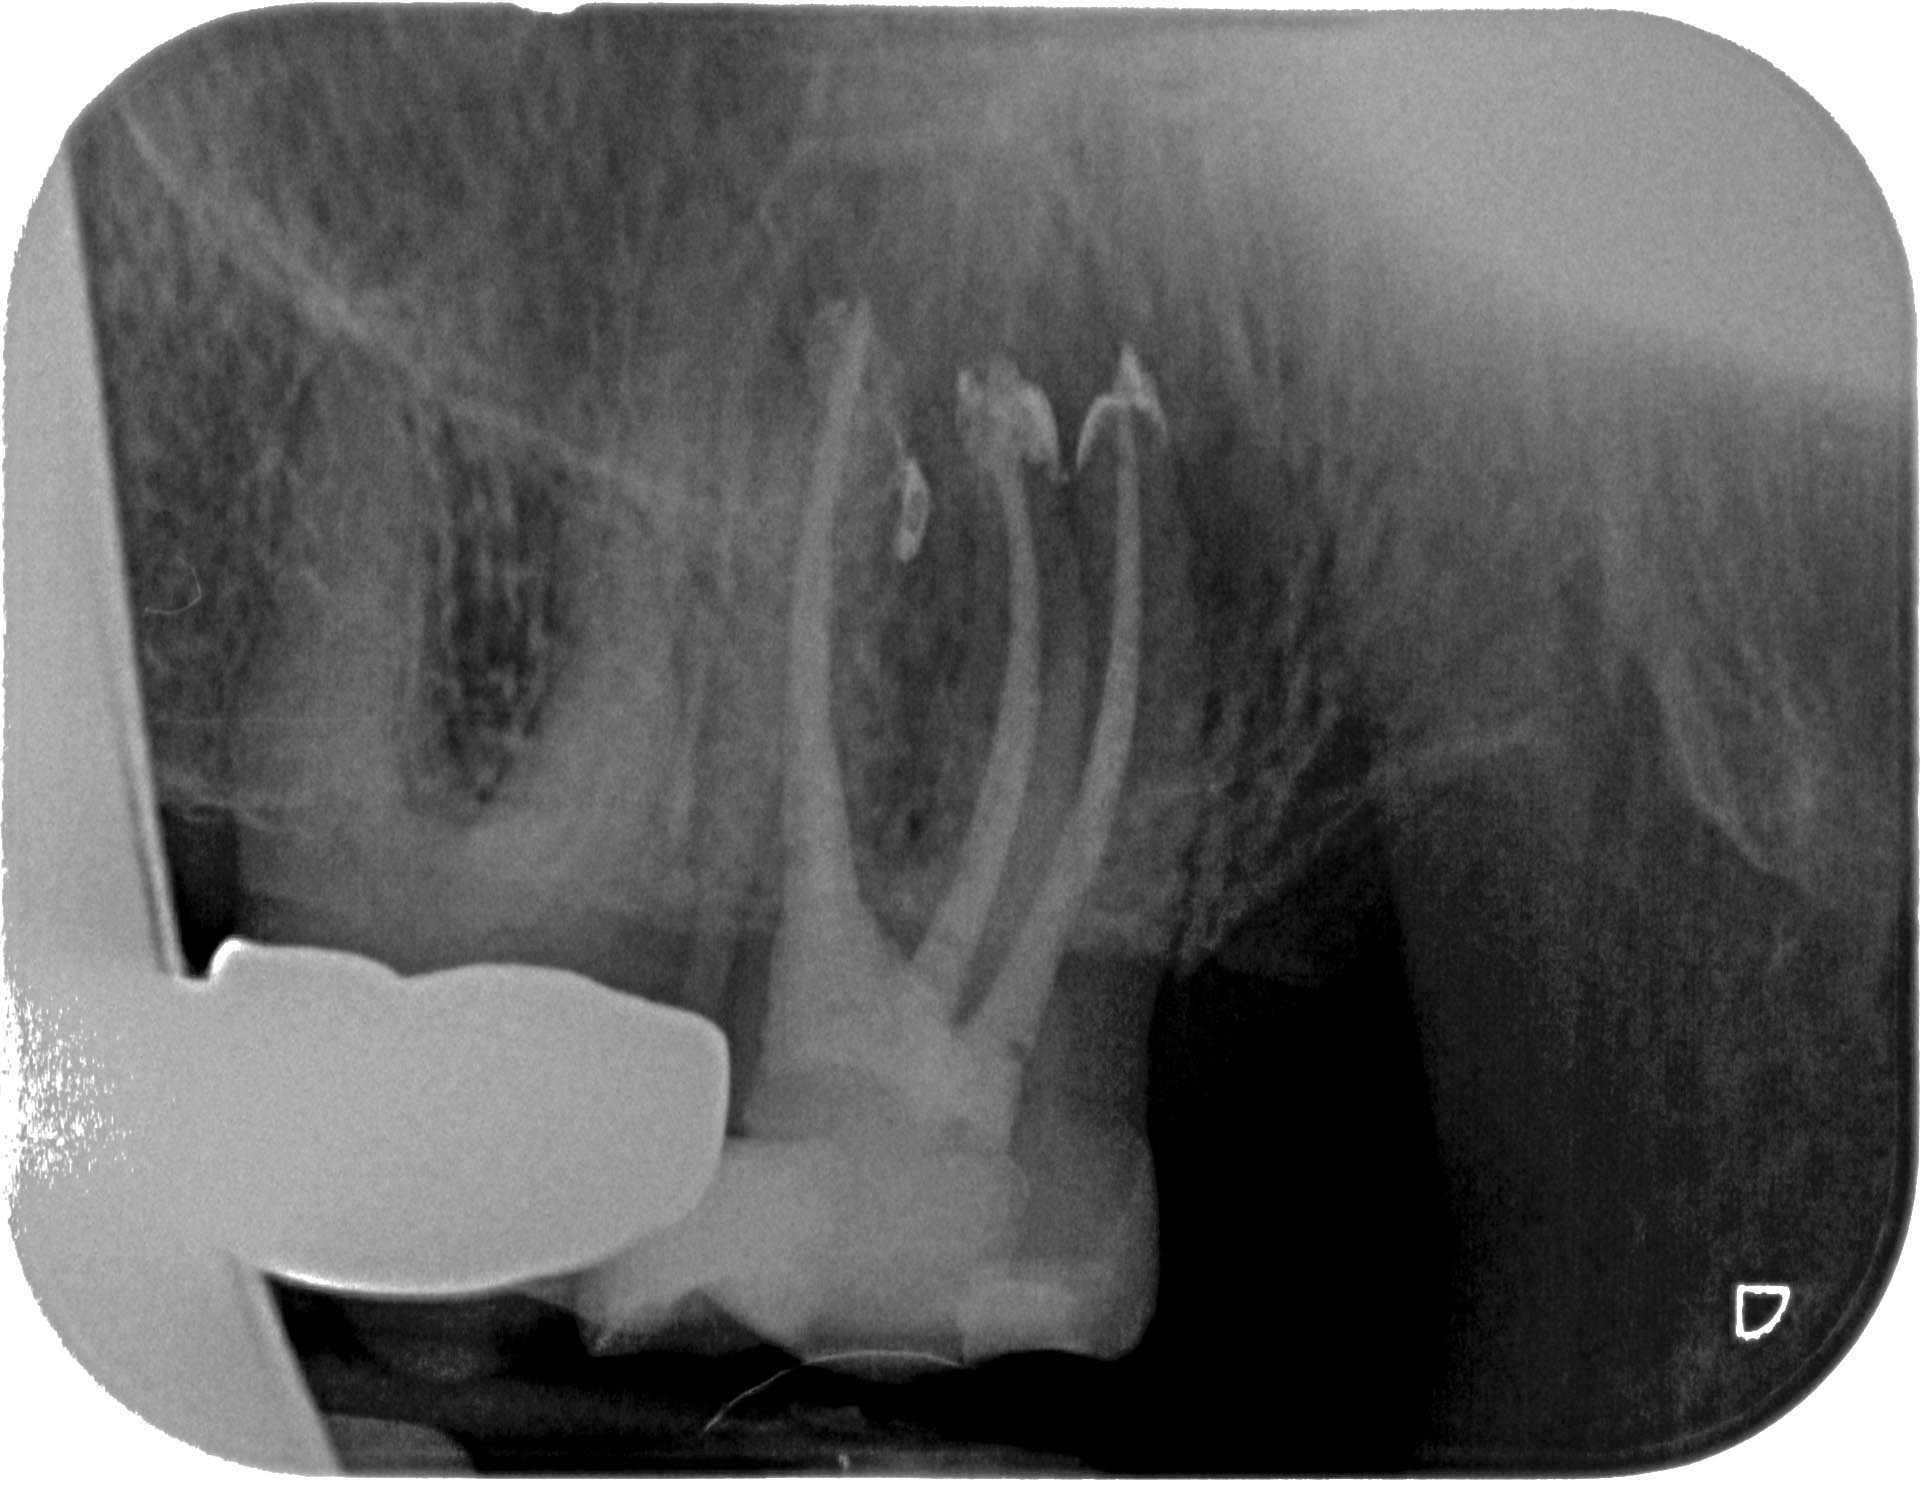

SE_27-4 Veröffentlicht 4. Mai 2014 am 1921 × 1486 in Massive apikale Aufhellung an Zahn 27 im Recall WF- Kontrolle 6 Monate post WF